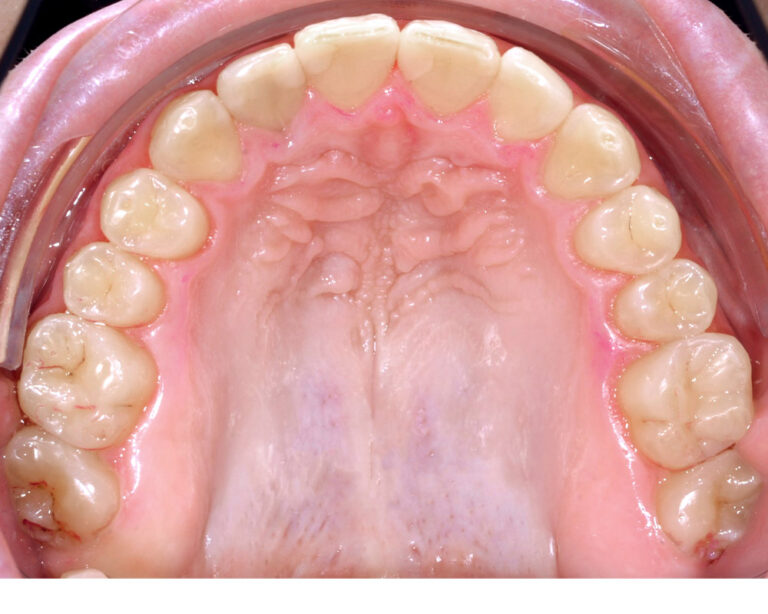

Открытый прикус - Кейс 2

Эффективность устранения дефекта прикуса посредством элайнеров FlexiLigner.

22

Количество кап НЧ

Количество кап ВЧ

Результаты лечения